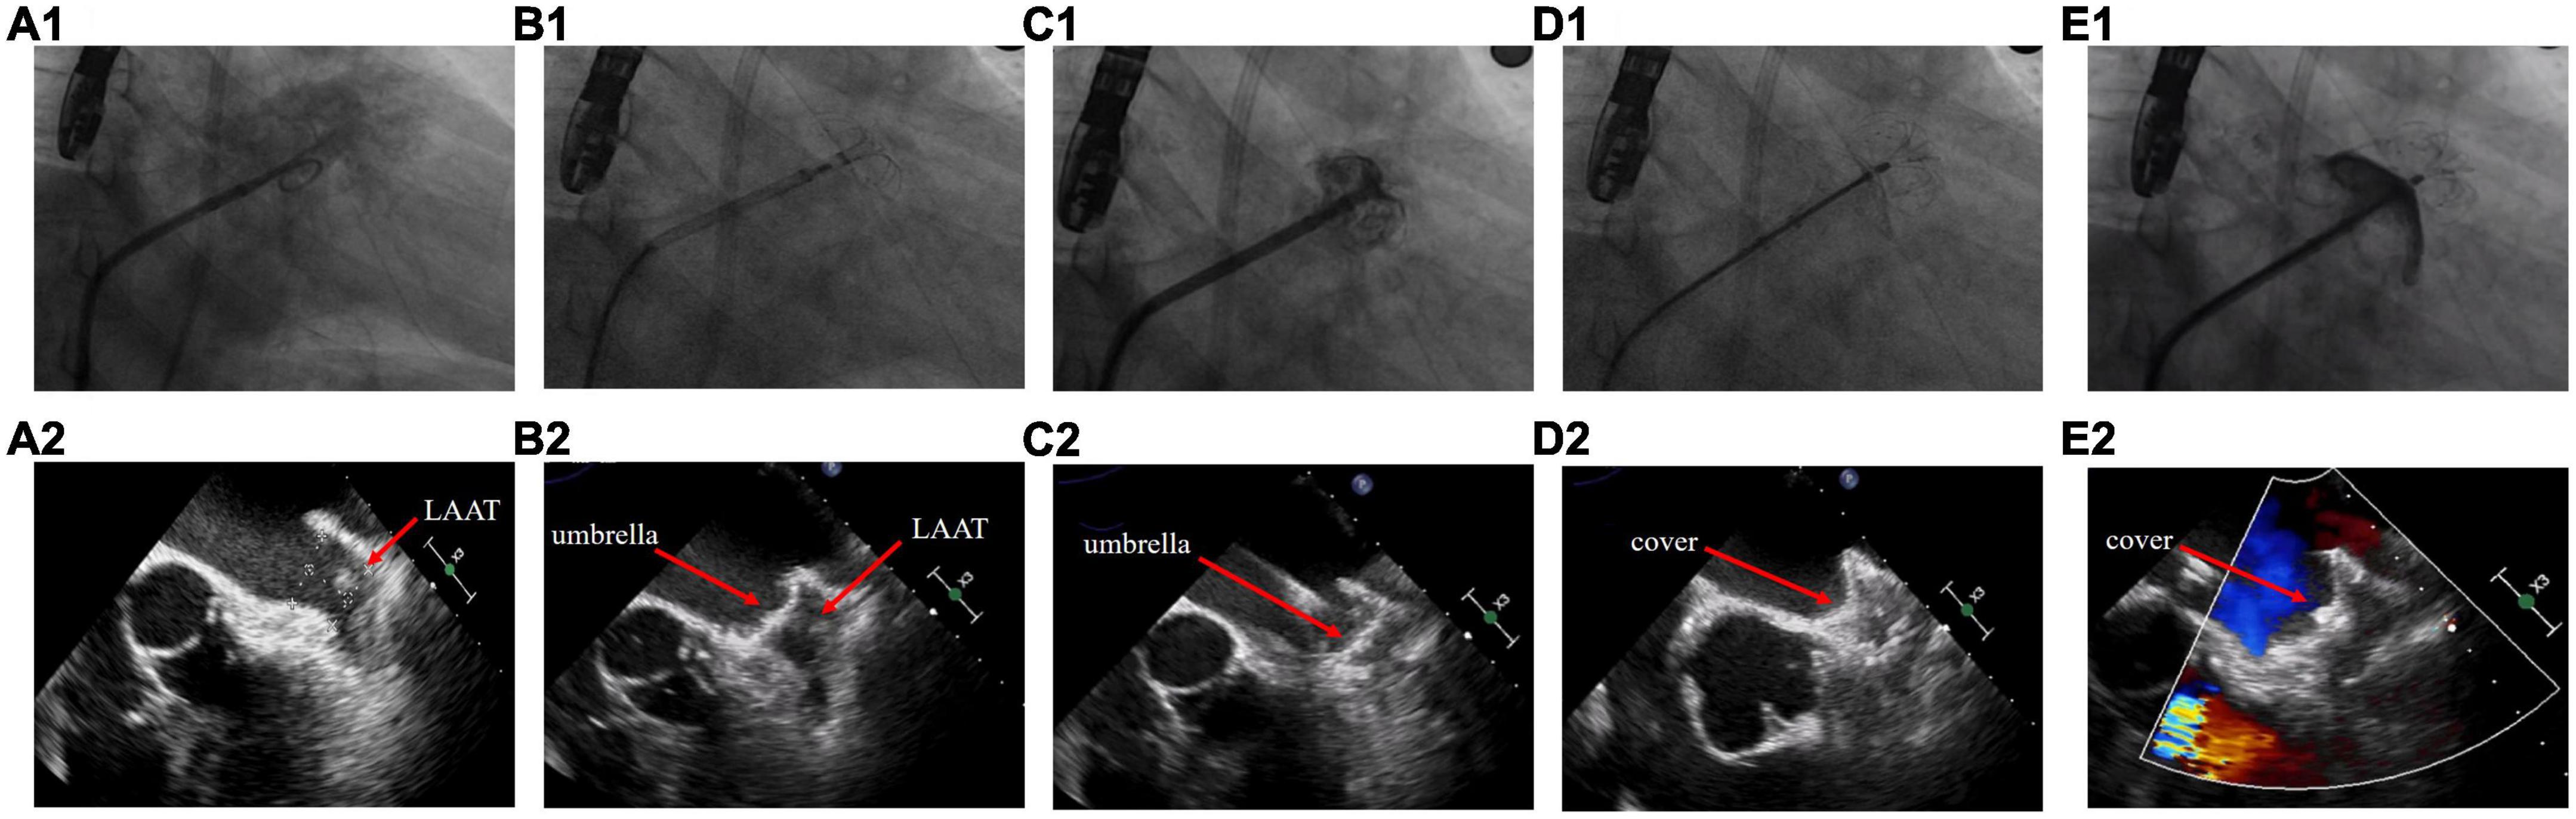

The procedures were performed under general anesthesia or local anesthesia. TEE was performed preoperatively to determine the location of the thrombus in relation to the LAA and the diameter of the device landing zone and LAA ostium. If any part of the thrombus was located between the landing zone and the LAA ostium, it was considered a proximal LAAT; otherwise, it was considered a distal LAAT. The choice of the device size and whether to use the cerebral protection system (Emboshield NAV6; Abbott Laboratories, Abbott Park, IL, USA) were at the discretion of the operator based on the TEE images. If the cerebral protection system was absent, a neurologic specialist would prepare for interventional treatment during the entire procedure. The procedure steps are as follows: (1) Transseptal access was obtained via the right femoral vein under fluoroscopic guidance, and a guidewire was slowly advanced into the left atrium. (2) The operator turned the Swartz sheath clockwise to facilitate the advancement of the guidewire into the left superior pulmonary vein. The guidewire must be manipulated carefully to avoid insertion of the LAA and contact with the LAAT. (3) The operator replaced the Swartz sheath with a delivery sheath and then delivered the pigtail catheter in the left superior pulmonary vein. (4) The operator dropped the pigtail catheter to the LAA ostium by slowly pulling the sheath and catheter back. Unlike the conventional LAAC procedure, the operator must keep the pigtail catheter in the sheath opening during this step to avoid random movement leading to thrombus dislodgement. (5) If the locational relationship between the pigtail catheter and the thrombus was appropriate, a small amount of contrast was injected to confirm the LAA anatomy. Intraoperative TEE was performed to reconfirm the location of the LAAT and accurately measure the LAA ostium and landing zone diameters for precise selection of the device size, which is critical to achieve a one-shot release. (6) The umbrella of the LAmbre device was initially two-thirds deployed at the ostium of LAA, and the whole system was then propelled under counterclockwise rotation to lock up the thrombus by pushing it to the distal part of the LAA. After advancement to the landing zone, the device subsequently completed deployment. The sheath was withdrawn to expand the proximal cover. (7) TEE, fluoroscopy, and a sustained tug test were then performed to confirm the proper position of the device and complete occlusion of the LAA. Finally, the device was released (Figure 1 and Supplementary Videos 1–12).

Figure 1. Left atrial appendage closure strategy in patients with left atrial appendage thrombus. (A) Fluoroscopy and transesophageal echocardiography images before the procedure. (B) The umbrella of the LAmbre device was partially deployed at the ostium of left atrial appendage (LAA). (C) The umbrella was propelled distally to the LAA and expanded. (D) The cover was deployed to seal the LAA ostium. (E) Detection of peridevice leak.